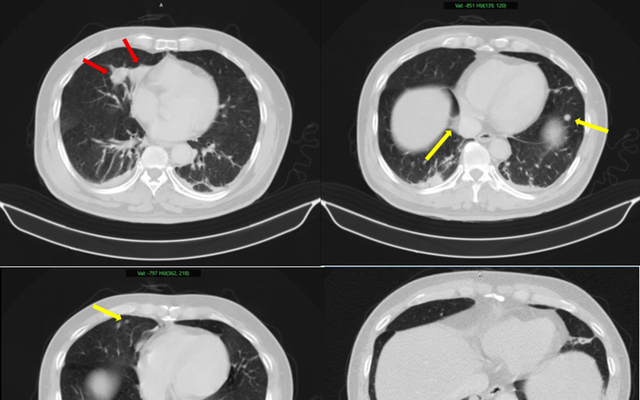

Hình ảnh 2 khối u bờ đa cung ở nhu mô thùy giữa phổi phải, dính vào màng phổi trung thất (mũi tên đỏ) kèm nhiều nốt đặc nhỏ rải rác nhu mô phổi hai bên (mũi tên vàng) gợi ý tổn thương thứ phát. Ảnh: BV Bạch Mai.